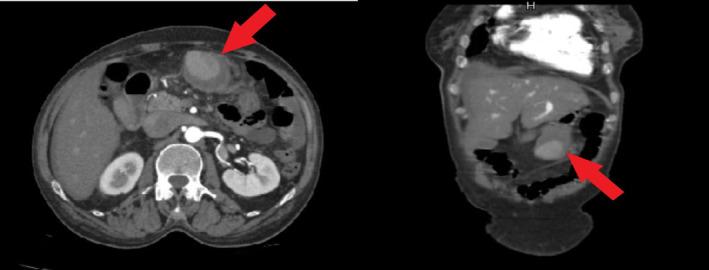

A 55-year-old woman with a history of coronary artery disease was referred to our hospital with abdominal pain as her primary complaint. Early works revealed anemia, a small amount of free peritoneal fluid, and a possible large aneurysm or pseudoaneurysm by the greater curvature of the stomach. She underwent emergency angiography that showed a large aneurism/pseudoaneurysm of the gastroepiploic artery. Successful embolization of the lesion was performed using the isolation technique. Perforation of a side branch of the gastroduodenal artery was observed on the immediate postembolization control angiography. Therefore, parent artery coiling was done immediately with good results. She was symptom-free and stable hemodynamically after the procedure, during the hospital course, and in the follow-ups.

一名有冠状动脉疾病史的55岁女性因腹痛为主诉被转诊至我院。早期检查发现贫血、少量腹腔游离液体,胃大弯处可能存在大动脉瘤或假性动脉瘤。她接受了急诊血管造影,显示胃网膜动脉有一个大动脉瘤/假性动脉瘤。采用隔离技术成功栓塞了该病变。栓塞后即刻控制血管造影观察到胃十二指肠动脉一分支穿孔。因此,立即对供血动脉进行了弹簧圈栓塞,效果良好。术后、住院期间及随访过程中她均无症状且血流动力学稳定。